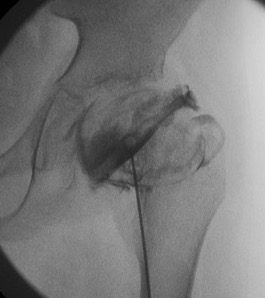

US

Nonspecific findings of synovitis usually found

- thickening synovial membrane vs. synovitis

- synovial effusion

CT

MRI

Advantage

- can assess amount of cartilaginous head outside of acetabulum

- very good way of assessing containment of cartilage head